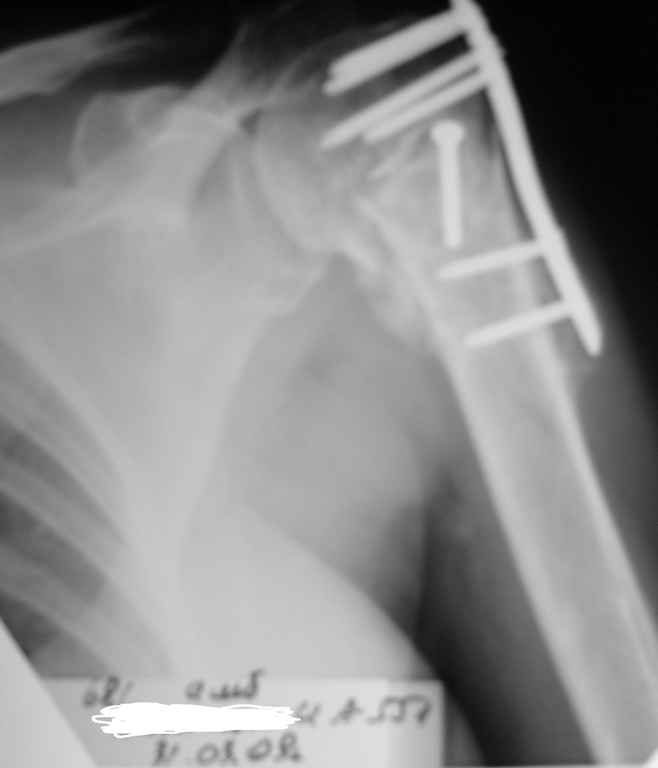

Пациентка Б.1953 г.р., врач-терапевт. Травма 27.11.08г. Падение с высоты роста. Выявлен закрытый не осложненный оскольчатый перелом хирургической шейки левого плеча со смещением. 02.12.08г. оперирована. Выполнена открытая репозиция и остеосинтез пластиной LCP Деост с дополнительной фиксацией отдельно лежащего фрагмента винтом. Послеоперационный период протекал без особенностей, заживление раны первичным натяжением. Швы сняты через 10 дней. Иммобилизация левой верхней конечности клиновидной подушкой 4 недели. По окончании срока – рентген-контроль и умеренная разработка плечевого сустава. В течении месяца функция левого плечевого сустава восстановилась удовлетворительно: поднятие руки до 110 гр., отведение - 90 гр. и до 110 гр. отведение с лопаткой. Отведение руки назад – 20 гр. Наружная и внутренняя ротация – 20 гр. Пациентка по настоянию самостоятельно вышла на работу. 27.03.09 при контрольном осмотре жалоб не предъявляет, болевой синдром в левом плечевом суставе отсутствует. Отведение плеча активно до 90 гр, пассивно с лопаткой до 110 гр., поднятие – 110 гр, отведение назад 20 гр, наружная и внутренняя ротация по 20 гр. На контрольных рентгенограммах отмечается смещение металлоконструкции, ротация головки плеча с приведением дистального отломка на 13 гр. и смещением к зади на 30 гр. Рентгенограммы прилагаются. Ваш взгляд на дальнейшую тактику лечения пациентки?

Рентгенограммы действительно с дефектом укладки, но интраоперационная репозиция, можете поверить, была удовлетворительная как в акcиальной, так и в сагиттальной плоскостях. Интраоперационная рентгенограмма прилагается, хотя укладка тоже на ахти. По тактике - разделяю Ваше мнение об отсутствии необходимости реостеосинтеза, а тем более об эндопротезировании, хотя это все было предложено пациентке ведущими ортопедами-травматологами России.

Здесь пример открытой репозиции 57 летнего с переломом плеча (1,2) смещение обнаружено на интероперационном снимке. При нормальной прямой проекция (3) угловое смещение обнаружили в аксиальной проекции (4)

После устранения смещения пластина установлена выше (5,6,7) и финальные снимки (8,9,10)